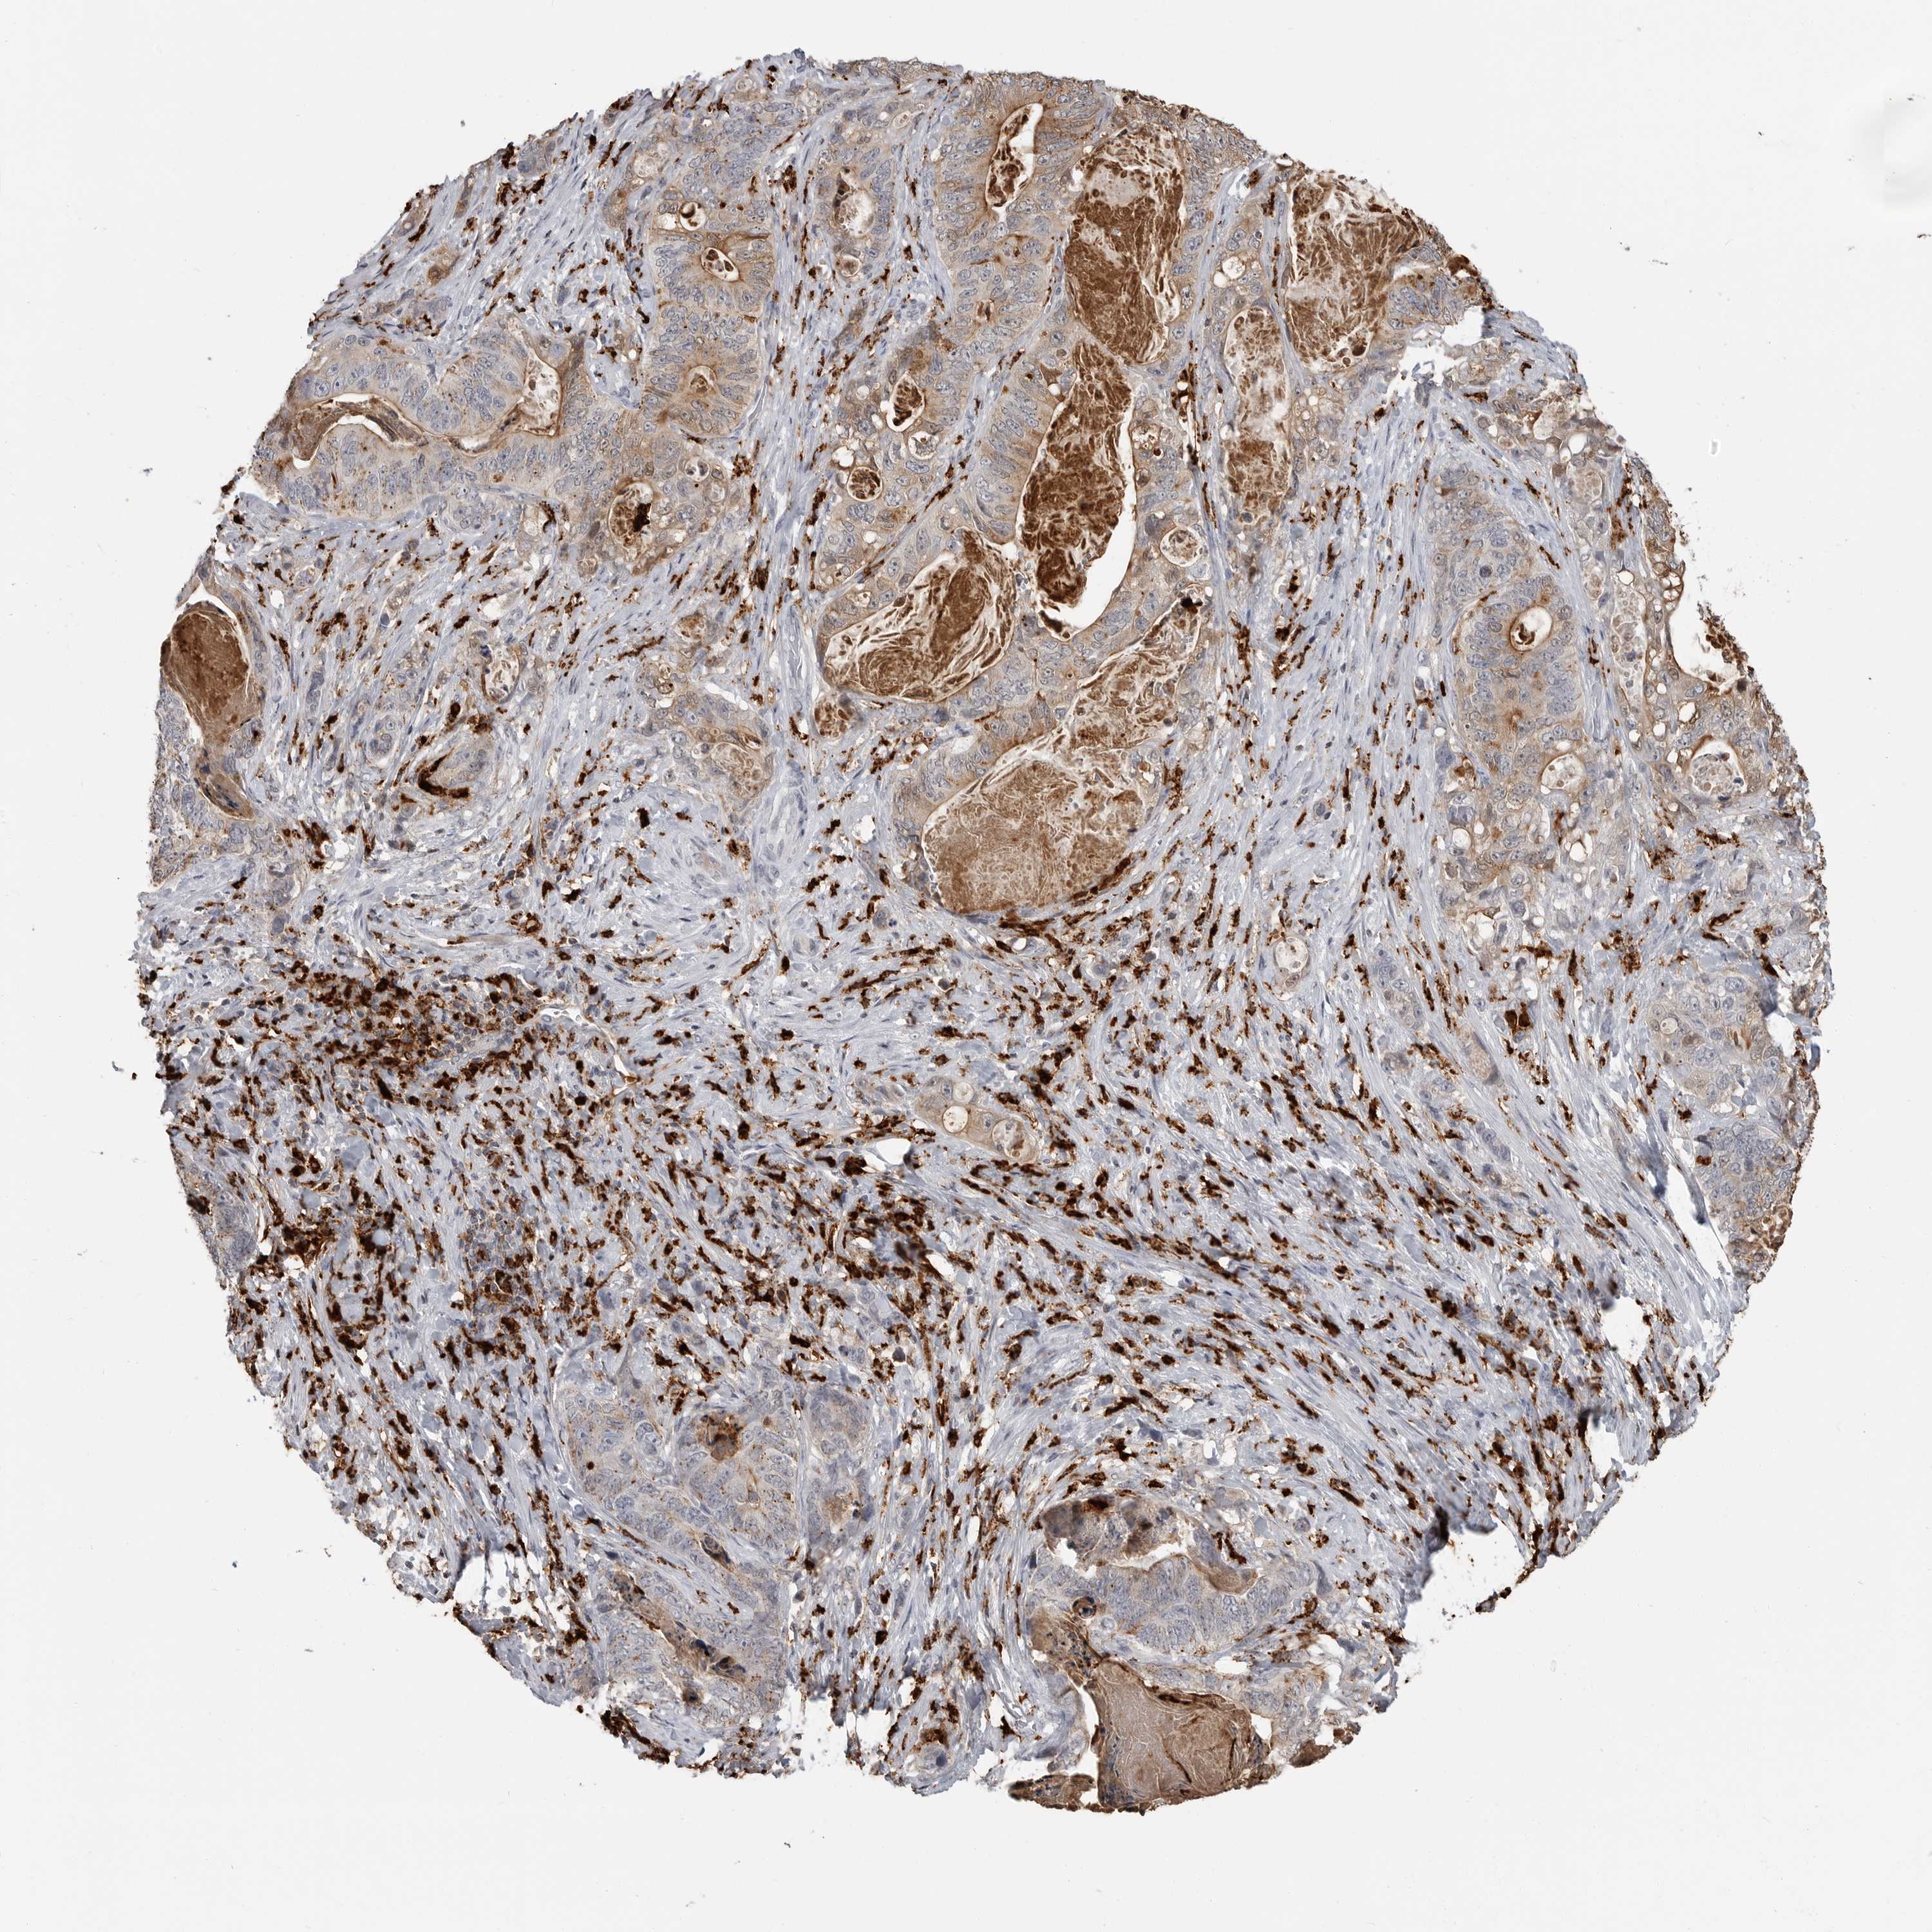

STOMACH CANCER - Protein expressioni

A mouse-over function shows sample information and annotation data. Click on an image to view it in a full screen mode. Samples can be filtered based on level of antibody staining by selecting one or several of the following categories: high, medium, low and not detected. The assay and annotation is described here.

Note that samples used for immunohistochemistry by the Human Protein Atlas do not correspond to samples in the TCGA dataset.

Antibody stainingi

Antibody staining in the annotated cell types in the current human tissue is reported as not detected, low, medium, or high, based on conventional immunohistochemistry profiling in selected tissues. This score is based on the combination of the staining intensity and fraction of stained cells.

Each image is clickable and will lead to virtual microscopy that enables deeper exploration of all samples and also displays staining intensity scores, fraction scores and subcellular localization as well as patient and tissue information for each sample.

Antibody HPA026650

Staining

High

Medium

Low

Not detected

Intensity

Strong

Moderate

Weak

Negative

Quantity

>75%

75%-25%

<25%

None

Location

Nuclear

Cytoplasmic/membranous

Cytoplasmic/membranous,nuclear

Adenocarcinoma, NOS